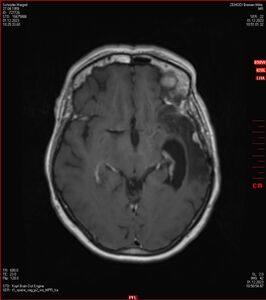

Zum Vergleich nun auch die Bilder vom 1.12.2023:

Ich denke, in den letzen 12 Monaten sind da ein paar Rezidive gewachsen,  vor 12 Monaten waren sie auch schon zu erkennen - vorher noch nicht. Nun hoffe ich auf den Rat des Spezialisten. Hoffendlich kann man etwas machen.